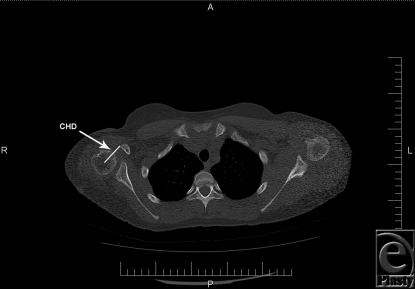

Twenty patients with deformities secondary to obstetric brachial plexus injury were included. Coracohumeral distances were measured on computed tomographic images. Clinical functioning was evaluated through video recordings by using a modified Mallet scale. Paired Student t tests were used to determine statistical significance of anatomic and functional parameters, pre- and postoperatively.

纳入20例继发于产瘫臂丛神经损伤的畸形患者。在计算机断层扫描图像上测量喙肱距离。通过使用改良的马利特量表的视频记录来评估临床功能。采用配对学生t检验来确定术前和术后解剖学和功能参数的统计学意义。